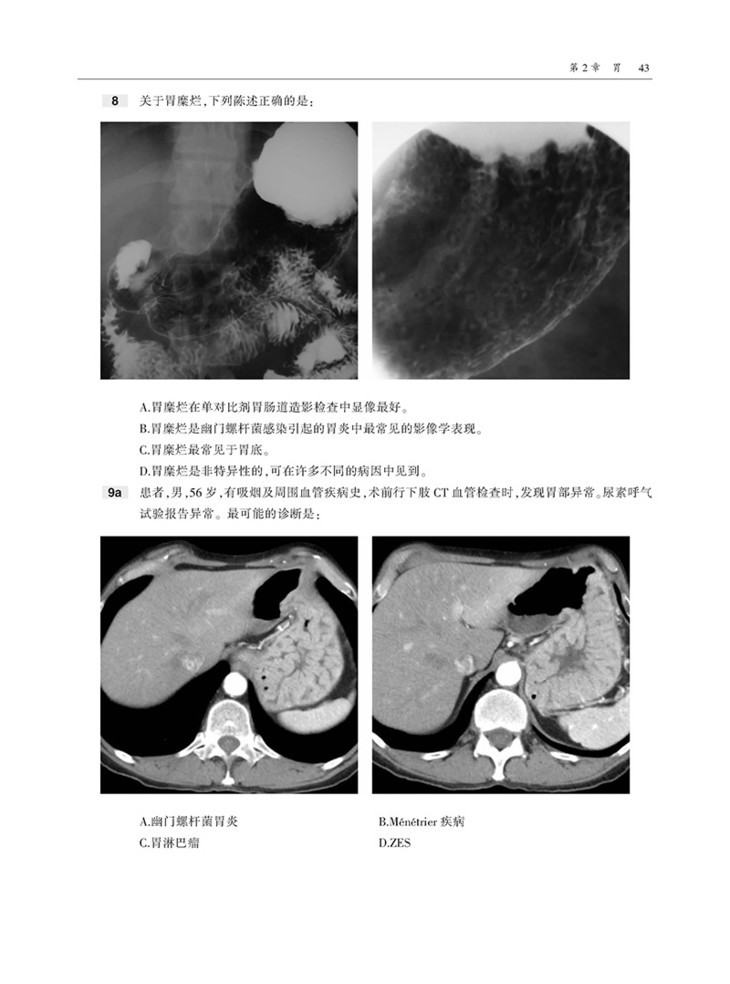

本书内容采用问答体例,首先给出患者病史和影像图片,然后列出问题和选项,便于读者独立思考,选择答案。各章末附有选择题答案和解析,正确选项和错误选项均有详细的注释,有助于读者加深理解和记忆。

囊括数百幅高清图像,直观显示病变的形态与特点等。